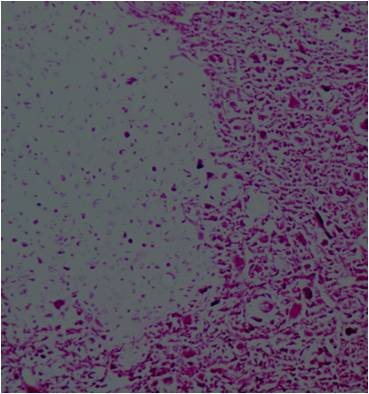

Microscopic Pathology

- Neoplastic cells may be small, round, oval, or spindle shaped

- Undifferentiated mesenchymal cells similar to Ewing sarcoma

- Low grade islands of cartilage scattered throughout the mesenchymal cells

- Usually only a small part of lesion

- Cytologically low grade

- Usually sharply demarcated from surrounding stroma

- Stain S-100 positive

- Cells within cartilage

- Tend to have round or ovoid nuclei

- Lacunae are poorly formed

- May contain islands of collagen resembling osteoid

- Lesions are vascular and often have large, anastomosing vessels that impart hemangiopericytoma-like pattern

(Right Arrow) Cartilaginous Component